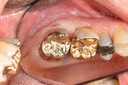

Gary Umeda #3-4 pre-op

Gary Umeda #29 pre-op

Gary Umeda #3 amalgam removal

Gary Umeda #3 prep

Gary Umeda #2,3,4 prep